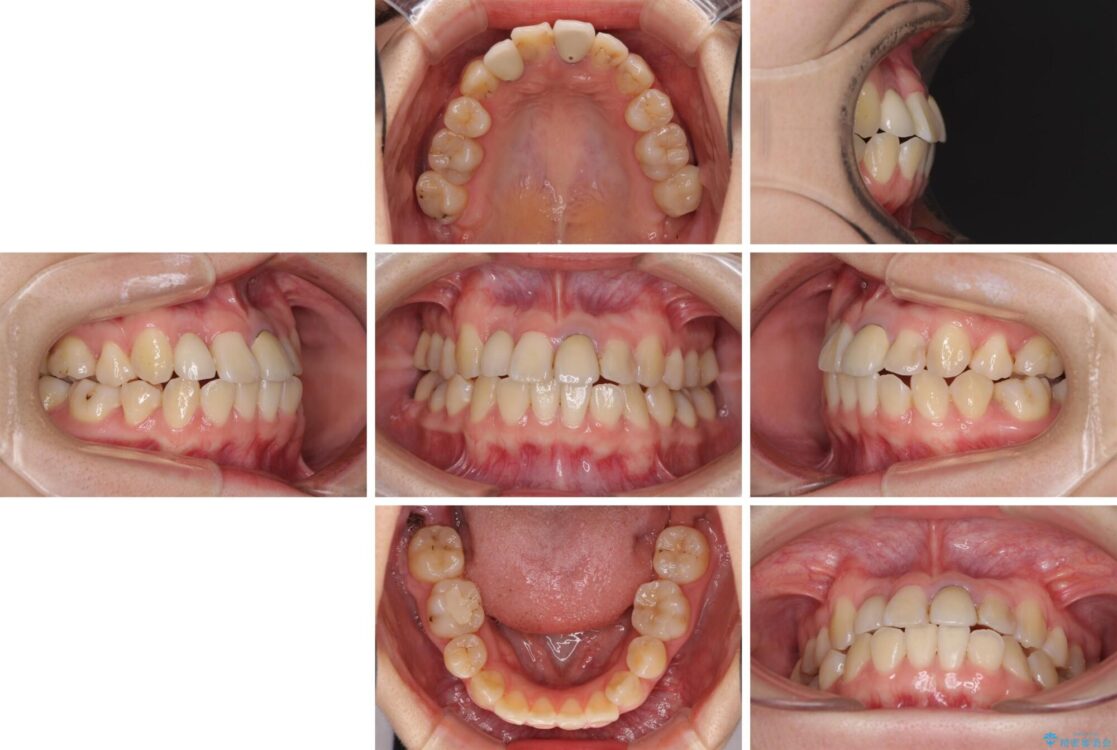

奥歯が痛いとのことで来院された患者様です。

治療計画

上顎親知らず周辺の炎症と、神経組織の失活した歯の炎症による痛みが認められたため、親知らずの抜歯と根管治療を行いました。

根管治療を行った歯はクラウンによる補綴治療が必要となりますが、高校生の頃に行った矯正治療の後戻りも気になるとのことで、補綴治療を行う前に矯正治療を行うこととしました。

後戻りは軽度であり、インビザラインにて歯列を整え、その後にオールセラミッククラウンにて補綴治療を行うこととしました。

治療前

治療途中

• 虫歯治療ついでに歯並びの後戻りを改善 インビザラインによる矯正治療 治療途中画像